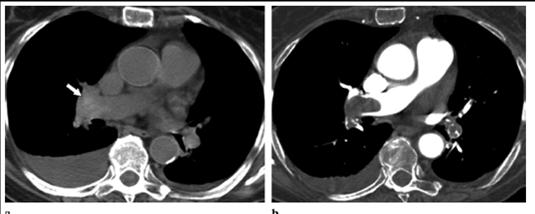

Hay que tener en cuenta que puede ocurrir que se detecte un TEP en un TC sin contraste que se realiza por otra causa o estudio que no sea para descartar TEP. En una obstrucción del arteria central, si observas una imagen de relleno con hiperatenuación, puede que estés ante una obstrucción por trombo. Ver imagen:

a) TC sin contraste, donde se observa aumento de la atenuación de la arteria central, compatible con trombo a dicho nivel. b) Confirmación con Angio-TC

a) TC sin contraste, donde se observa aumento de la atenuación de la arteria central, compatible con trombo a dicho nivel (ver flecha blanca).

b) Confirmación con Angio-TC